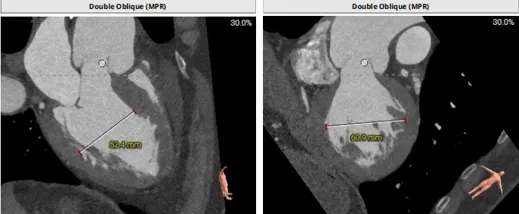

主动脉根部测量

周长74.4 周长径23.7

周长83 周长径26.4

42.4mm&41.1mm&46.5mm

周长147.2 周长径46.9

周长146.5 周长径46.7

心脏角度:53°

瓣上结构测量

周长77.3 周长径24.6

周长82.8 周长径26.4

周长92.8 周长径29.5

周长98.2 周长径31.3

瓣膜型号:ScienCrown TAVTF27mm(oversize13.92%)